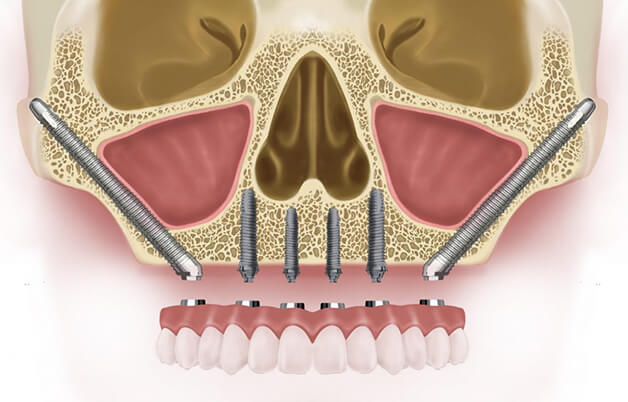

- Базальная и скуловая — применяют при недостаточности костной ткани без ее наращивания. Импланты особой конструкции вживляются в глубокие слои челюстной кости, которые отличаются большей плотностью и не подвержены атрофии.

- При полном отсутствии зубов (адентии) — вживление стержней для установки на них протезов по протоколам All-on-3, All-on-4, All-on-6, а также базальная и скуловая имплантация.

На верхней челюсти операция по восполнению недостающей высоты кости в боковых отделах в области гайморовых пазух называется синус-лифтинг. Бывает 3-х видов:

- Закрытый (вертикальный, малый) синус-лифтинг. Проводится в случае, когда массив костного материала в челюсти пациента достигает 7-8 мм в высоту. В некоторых ситуациях может быть выполнен одновременно с имплантацией. Но пациенту следует избегать немедленной нагрузки на новый корень — ее надо увеличивать очень аккуратно.

- Открытый (латеральный, большой) синус-лифтинг. Актуален при существенной атрофии кости, когда ее высота менее 7 мм. Наращивание проводят отдельно от имплантации, поскольку требуется достаточно много времени для приживления искусственной костной массы. Имплант ставится не раньше, чем через 20 недель после операции.

- Баллонная аугментация. Показана в случае большого дефицита костной массы. Метод напоминает закрытый синус-лифтинг, но в данном случае под слизистую оболочку вместо гранул помещают баллончик с жидкостью. По мере увеличения баллона в размерах происходит отслоение слизистой в щадящем режиме. Образовавшуюся полость заполняют искусственным костнопластическим материалом. Имплант устанавливают сразу после операции.

Еще один вид костной пластики — синуспак (антропластика). Метод предполагает:

- пластику альвеолярного отростка;

- заполнение повторно созданного объема синуса одним из биопластических материалов или их комбинацией.

В зависимости от применяемого костнозамещающего материала, сроки приживления составляют от 4-6 до 12-18 месяцев.

Пример клинического случая

Пациент в результате аварии получил травму, и потребовалась имплантация зубов. Вначале было проведено экспериментальное обследование и при помощи компьютерной томографии получены снимки челюсти. Затем хирург выполнил операцию по наращиванию и частичному замещению костной ткани — закрытый синус-лифтинг с одномоментным вживлением 4-х имплантов.

Через месяц выполнено временное протезирование. Спустя еще 6 месяцев сделали контрольный рентгеновский снимок челюсти пациента для подтверждения приживления новых тканей и искусственного корня. В завершение стоматолог установил постоянные металлокерамические коронки, имитирующие натуральные зубы (изготовление заняло не более 2-х недель).